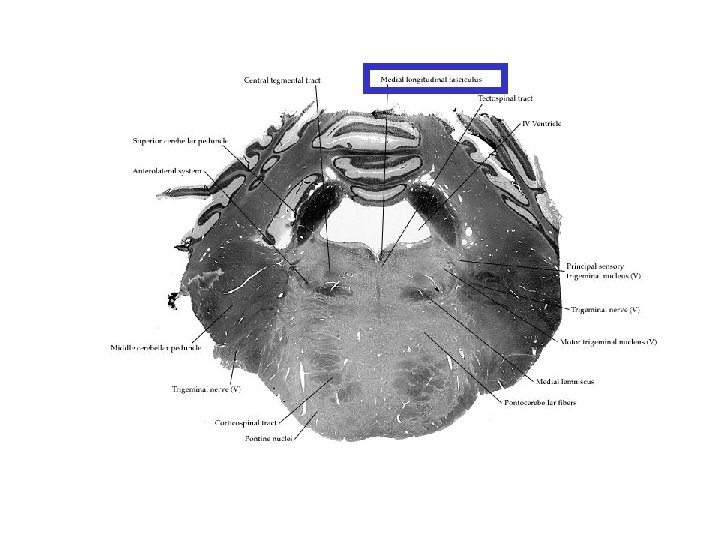

PONS: 2. kesit (N. trigeminus seviyesi)

Fasciculus longitudinalis medialis Orta çizgiye çok yakın olarak yer alır. Kafa çiftlerinin birbirleri ile olan bağlantısını sağlar Beyin sapında göz kaslarını inerve eden çekirdekler arasında ve bu çekirdekler ile vestibular sistem arasında önemli rol oynar.